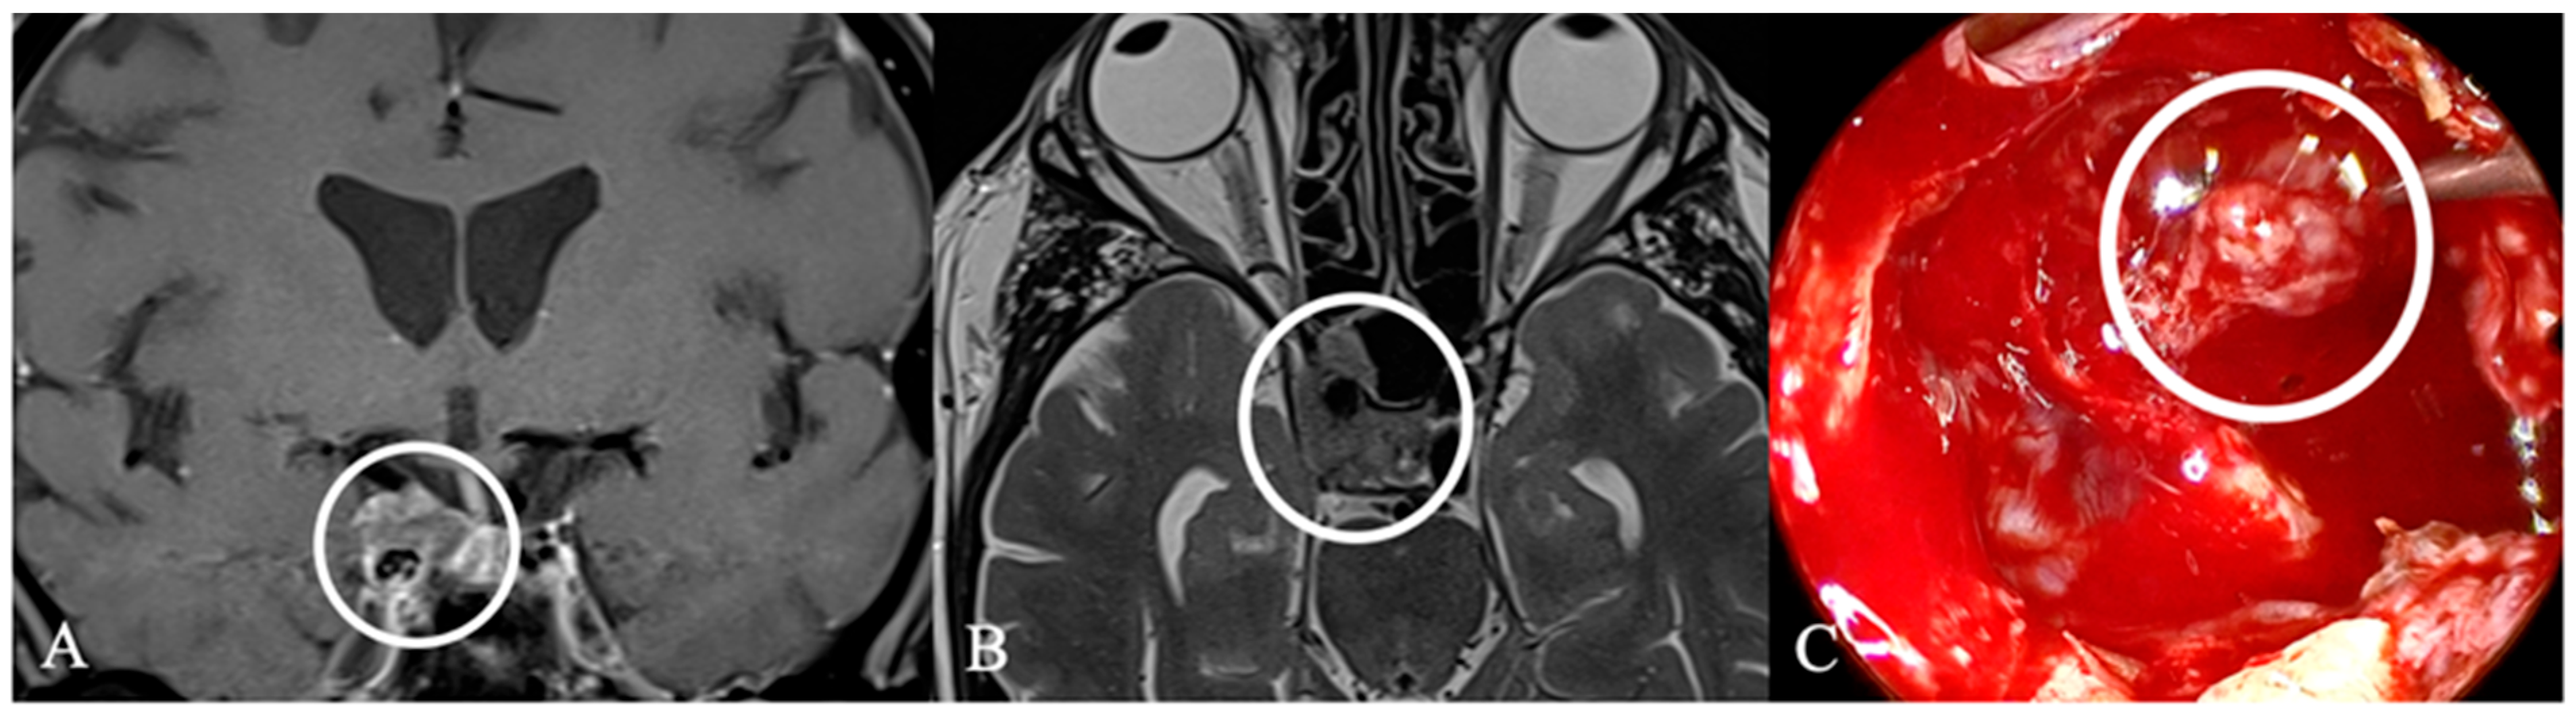

4.2. Differential Diagnoses and Case Presentations